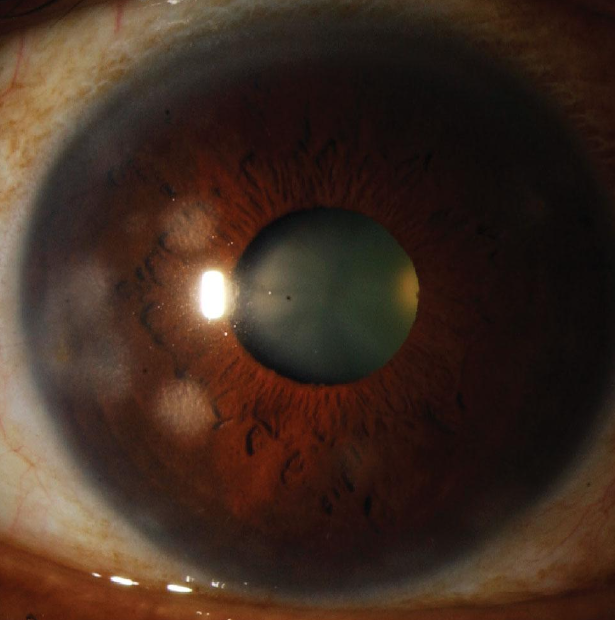

Saber qué buscar durante el examen le ayudará a determinar el tipo de virus. “Si está en la superficie de la córnea, esto es clásicamente lo que vemos en los libros como una dendrita de herpes simple. Es una forma muy específica, no se la puede perder”, dice Bennie Jeng, MD, director del departamento de oftalmología y director del Scheie Eye Institute, en Penn Medicine, en Filadelfia.

“La queratitis epitelial se presenta con dendritas lineales con ramas que presentan bulbos terminales distintos. Para confirmar este diagnóstico, debe usarse la tinción con fluoresceína en el centro de las dendritas y la de rosa de bengala en la periferia – esa es la clásica tinción de la dendrita”, dice la Dra. Tuli. El problema con el simple es que no solo causa dendritas, puede causar infección en cualquiera de las capas de la córnea e, incluso, en la cámara anterior”, dice. “Estas se vuelven un poco más difíciles de diagnosticar porque la inflamación del estroma se puede pasar por alto. Puede manifestarse como estos pequeños parches borrosos en la córnea, y si no los tratas, entonces los vasos sanguíneos pueden comenzar a crecer en la córnea y causar queratitis pannus o intersticial”.

Las dendritas para HZO se ven sutilmente diferentes. “Las dendritas de zóster (conocidas como pseudodendritas) tienen bordes cónicos y carecen de los distintos bulbos terminales”, dice Deepinder K. Dhaliwal, MD, LAc, profesora de oftalmología de la Universidad de Pittsburgh.